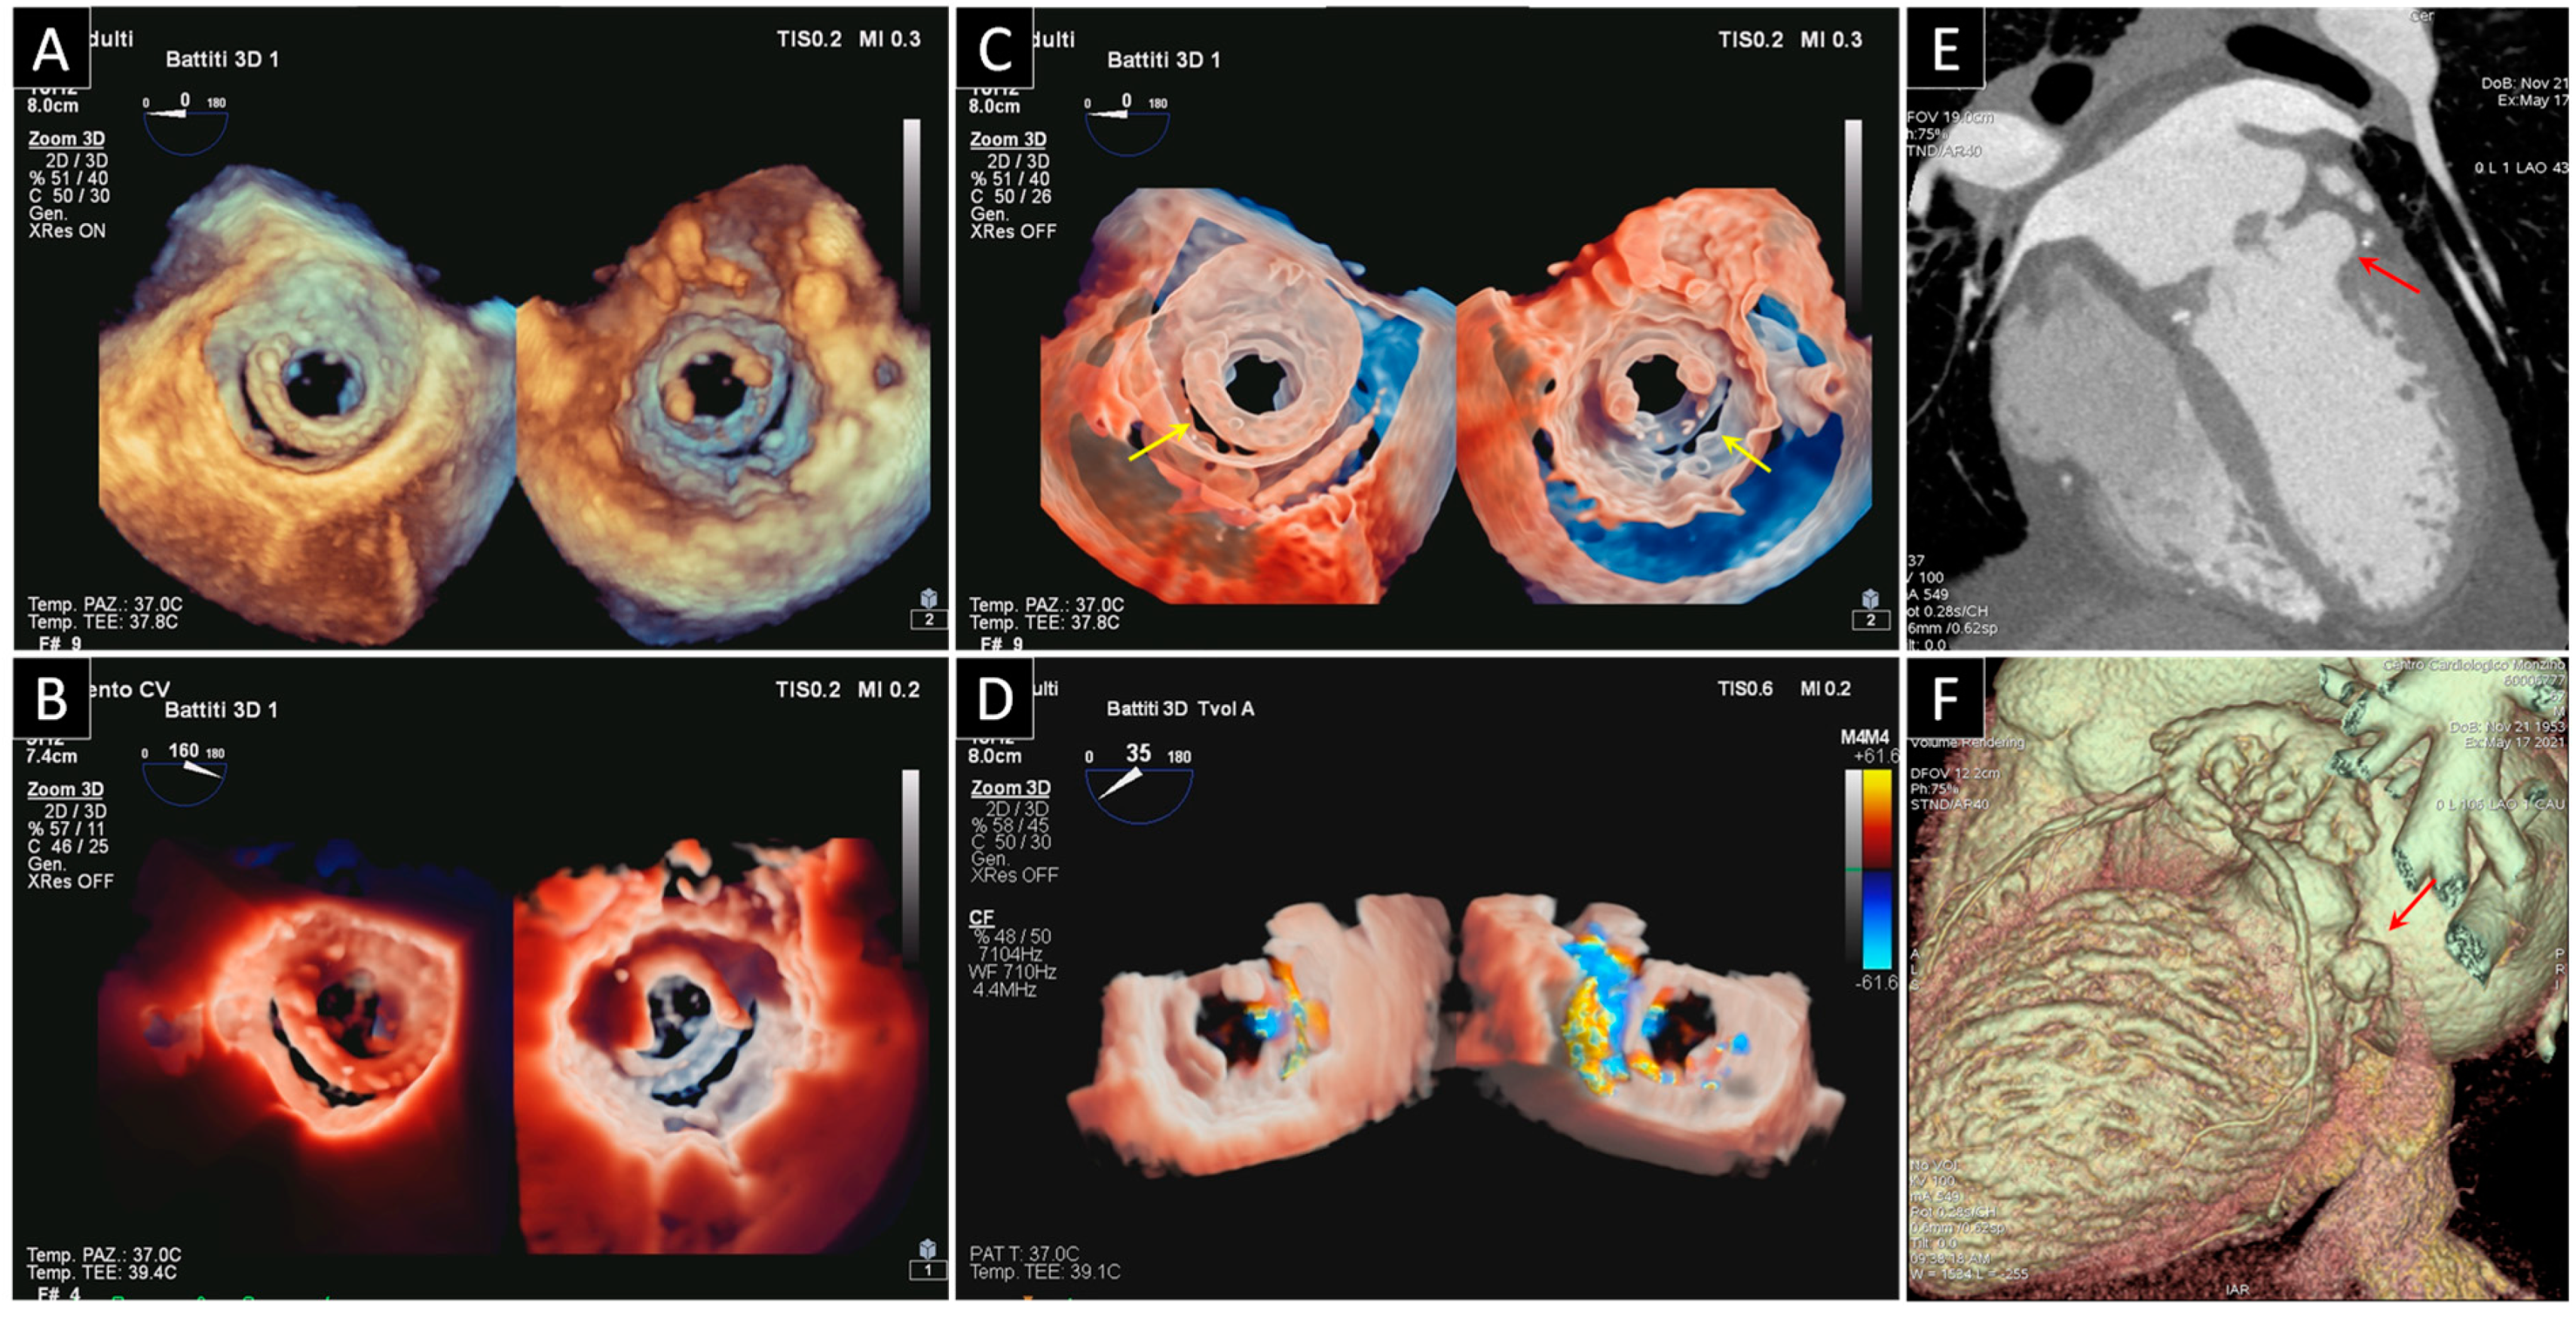

2. Prosthetic Valve Obstruction

2.1. Prosthetic Mitral Valve Obstruction

2.2. Prosthetic Aortic Valve Obstruction

3. Prosthetic Paravalvular Leak

3.1. Mitral Paravalvular Leak

3.2. Aortic Paravalvular Leak